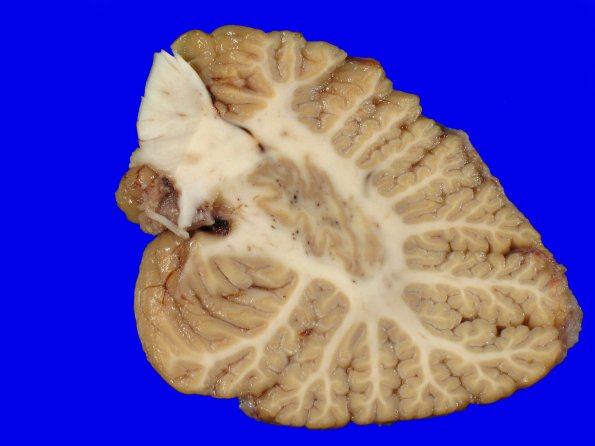

10B3 NCL (Case 10) Gross_26

There was minimal cerebellar atrophy.